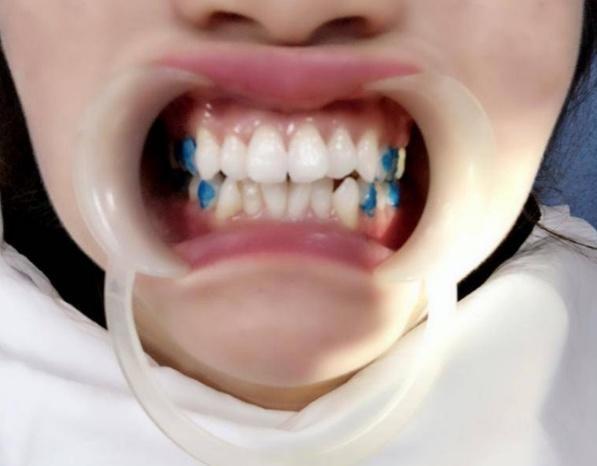

牙套做好后,醫(yī)生給我做了片切,還粘了附件(就在上圖涂藍色的牙齒上面)。據(jù)說這些精細的工作考驗醫(yī)生的技術(shù),我發(fā)現(xiàn)我的醫(yī)生操作起來熟練。我的牙齒也沒有覺得有啥敏感或不舒服的,全程都可以接受。